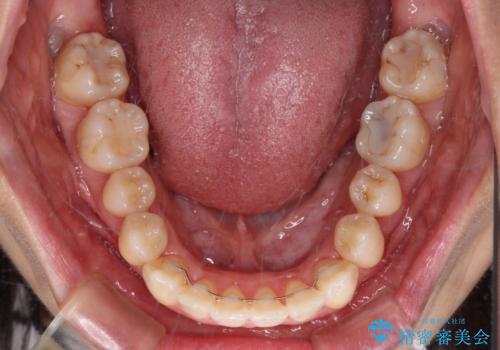

1. 【モニター】急速拡大装置 狭い歯列を拡大してワイヤー装置で短期間治療の治療前